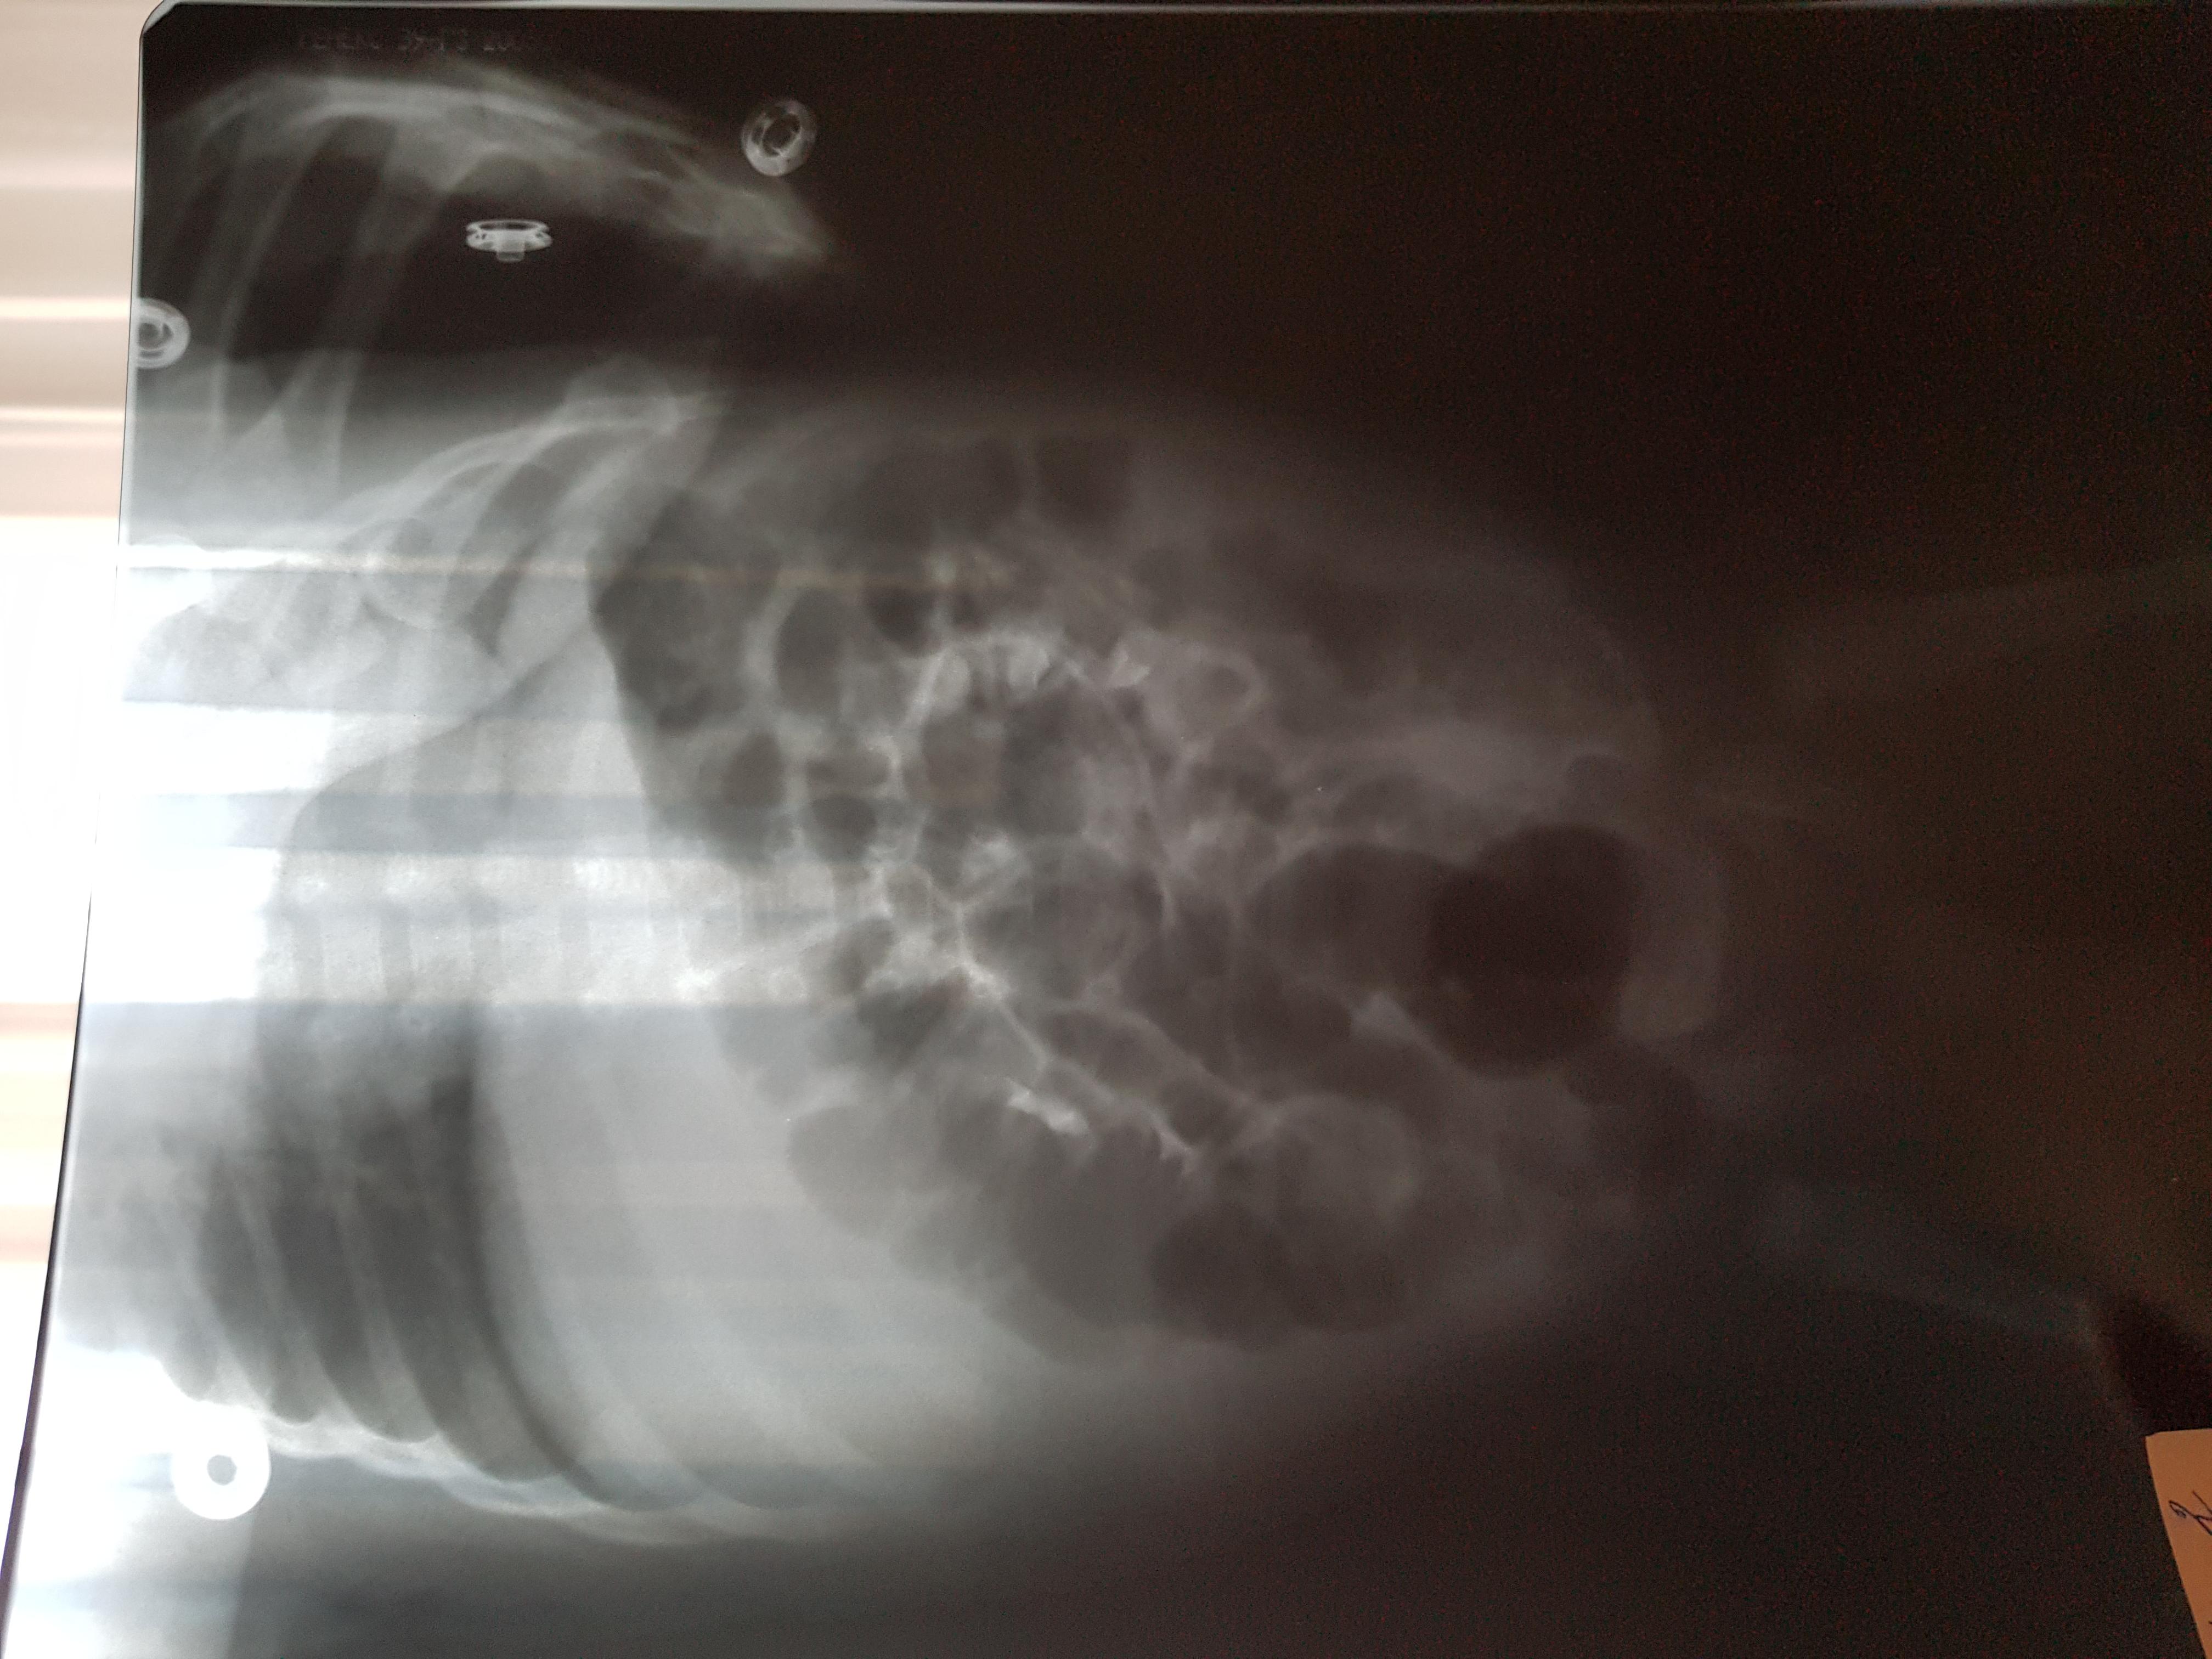

Добрый день! Еще внутриутробно у ребенка обнаружили расширение лоханок.Провели обследование в 1.5 месяца.Поставили диагноз болезнь Ормонда.И назначили консервативное лечение.В 2ух мочеточниках по несколько наростов.рефлюкса не было.Скажиье, возмлжнл что ребенок поосто перерастет?

Болезнь Ормонда (ретроперитонеальный фиброз, забрюшинный фиброз) – хроническое воспаление жировой клетчатки забрюшинного пространства, которое постепенно приводит к компрессии и нарушению проходимости трубчатых структур данного анатомического участка. Чаще всего, в качестве этих тубулярных структур выступают мочеточники.

У меня есть сомнения, что причиной гидронефроза в Вашем случае явилось именно это состояние.